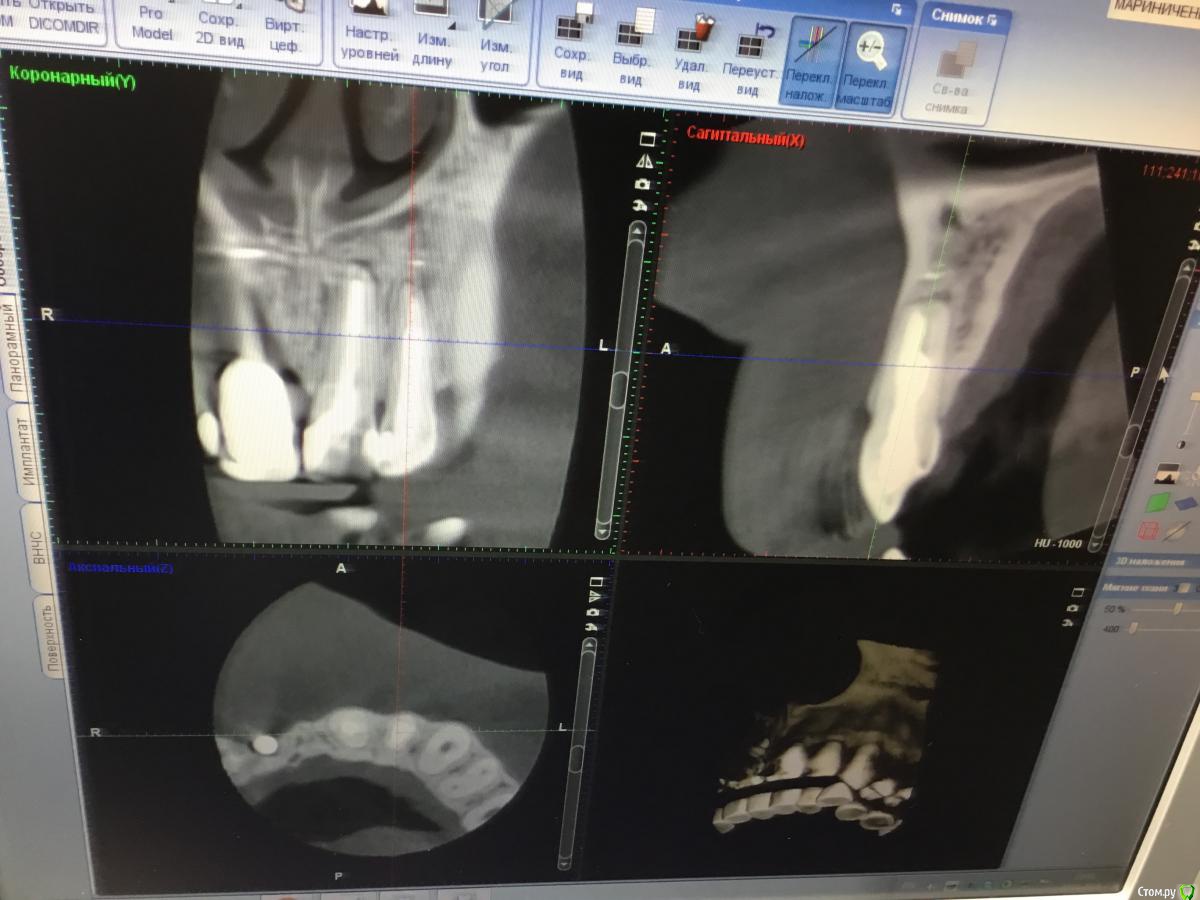

Zorrro Опубликовано 6 марта, 2016 Поделиться Опубликовано 6 марта, 2016 (изменено) Мой постоянный пациент привёл своего сынишку с жалобами на свищь на нёбе.Сделали кт и решили ,что вначале переберём каналы,а через пол года будем посмотреть куда нам двигаться дальше… Эстетика коронки на 11 вполне устраивала пациента,тем более он был уверен,что поставилимплант и вследствии коронку популярный доктор используя новейшие технологии и материалы,позволяющие не прибегать к устаревшим костным и ещё каким-то пластикам.запись к доктору уходила на пол года вперёд и молодой человек чудом втиснулся в этот плотный график,чтобы отхватить немножко и себе этих самых "новейших" технологий под нос. Фото ещё раз показывает,чтосамое главное в успехе частной практики это ВЕРА доктора в себя и то,что он делает.меня же коронка устраивала тем более,потому что переделывать её вместе с имплантом мне крайне не хотелось.обошлись комментарием про усиленную гигиену и регулярные наблюдения раз в пол года. итак занялись посильным трудом:отмыли 21 и 22,констрикция убежала за 50.02,остановились на 70.02 стальными файлами отступя 1мм,метапекс,через 2 недели irm и стекловолокно нафуджи+,филтек.договорились про контроль через пол года и коронки если всё ок. Ещё немного срезов до и преимущество кт перед прицельными снимкамиИ сразу после. Про коронки и корневой герметизм пациент не понял и решил оставить бломбы на месте. Изменено 6 марта, 2016 пользователем Zorrro 1 Ссылка на комментарий